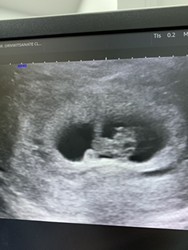

9 W เจอน้องกันยังคะแม่ๆ หมอบอกน้องยังตัวเล็กอยู่อาจจะไม่ค่อยชัดของแม่แต่ละบ้านเป็นงัยกันบ้างคะ